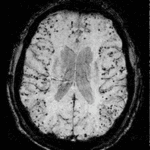

- CTH:

- Continous video EEG ordered